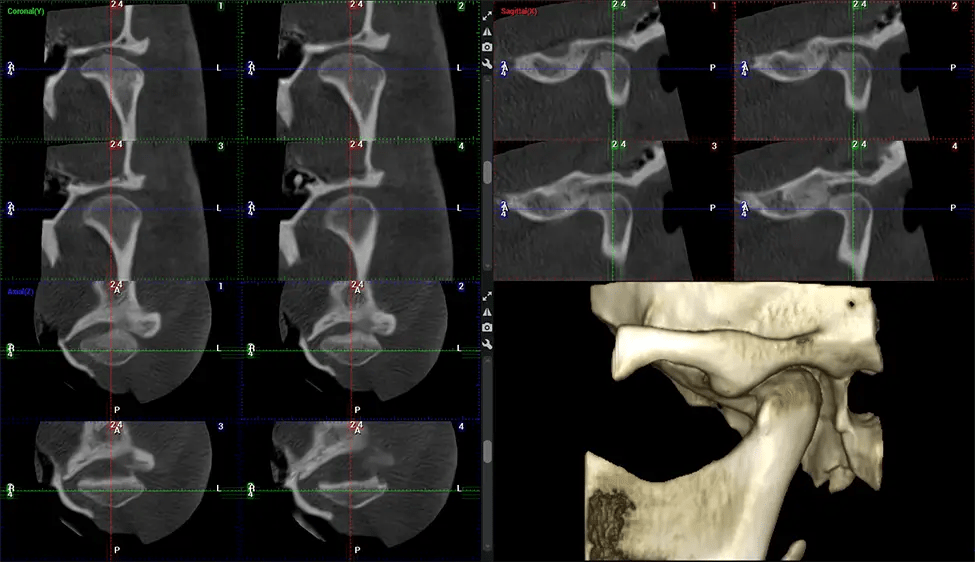

Primero se coloca al paciente en el escáner CBCT, que normalmente consta de un brazo giratorio que alberga la fuente de rayos X y un detector. La cabeza del paciente está inmovilizada para garantizar una captura de imágenes precisa. La fuente de rayos X y el detector giran alrededor de la cabeza del paciente, capturando varias imágenes de rayos X desde múltiples ángulos. A medida que la fuente de rayos X gira, emite un haz de rayos X en forma de cono hacia el detector. El detector captura las imágenes de rayos X, que luego son procesadas por el software CBCT.

Después del proceso de escaneo, las imágenes de rayos X capturadas son procesadas por el software CBCT, que aplica algoritmos para reconstruir una imagen 3D detallada del área escaneada. El software recopila estas imágenes de rayos X individuales y crea una representación digital en 3D de la anatomía del paciente. El dentista o el radiólogo pueden ver y analizar la imagen CBCT 3D reconstruida. Esta imagen se puede manipular, rotar y acercar o alejar para examinar estructuras específicas y evaluar la condición del paciente.

Planmeca Viso G7 CBCT (Cone Beam CT Scan) está diseñado para superar las demandas de los líderes de la industria, los especialistas y las grandes instituciones. Tiene un gran sensor de ø25×30 cm con cuatro cámaras integradas. Puede capturar tamaños de volumen ilimitados, desde ø3×3 cm hasta ø30x30cm, capturando el casquete escutelario a través de C7 en la columna cervical. Planmeca Viso G7 ofrece el escaneo de volumen único más grande de la industria de ø30×19 cm. Está preparado para manejar modalidades de imágenes avanzadas como la tecnología Planmeca ProFace® y Planmeca 4D™ Jaw Motion. El soporte occipital para la cabeza permite una visión sin obstáculos del tejido facial.

Las unidades Planmeca 3D también incluyen la única tecnología de corrección y detección de movimiento del paciente de la industria, Planmeca CALM™. Esta tecnología corrige el movimiento durante la adquisición de CBCT reduciendo el riesgo de repeticiones.